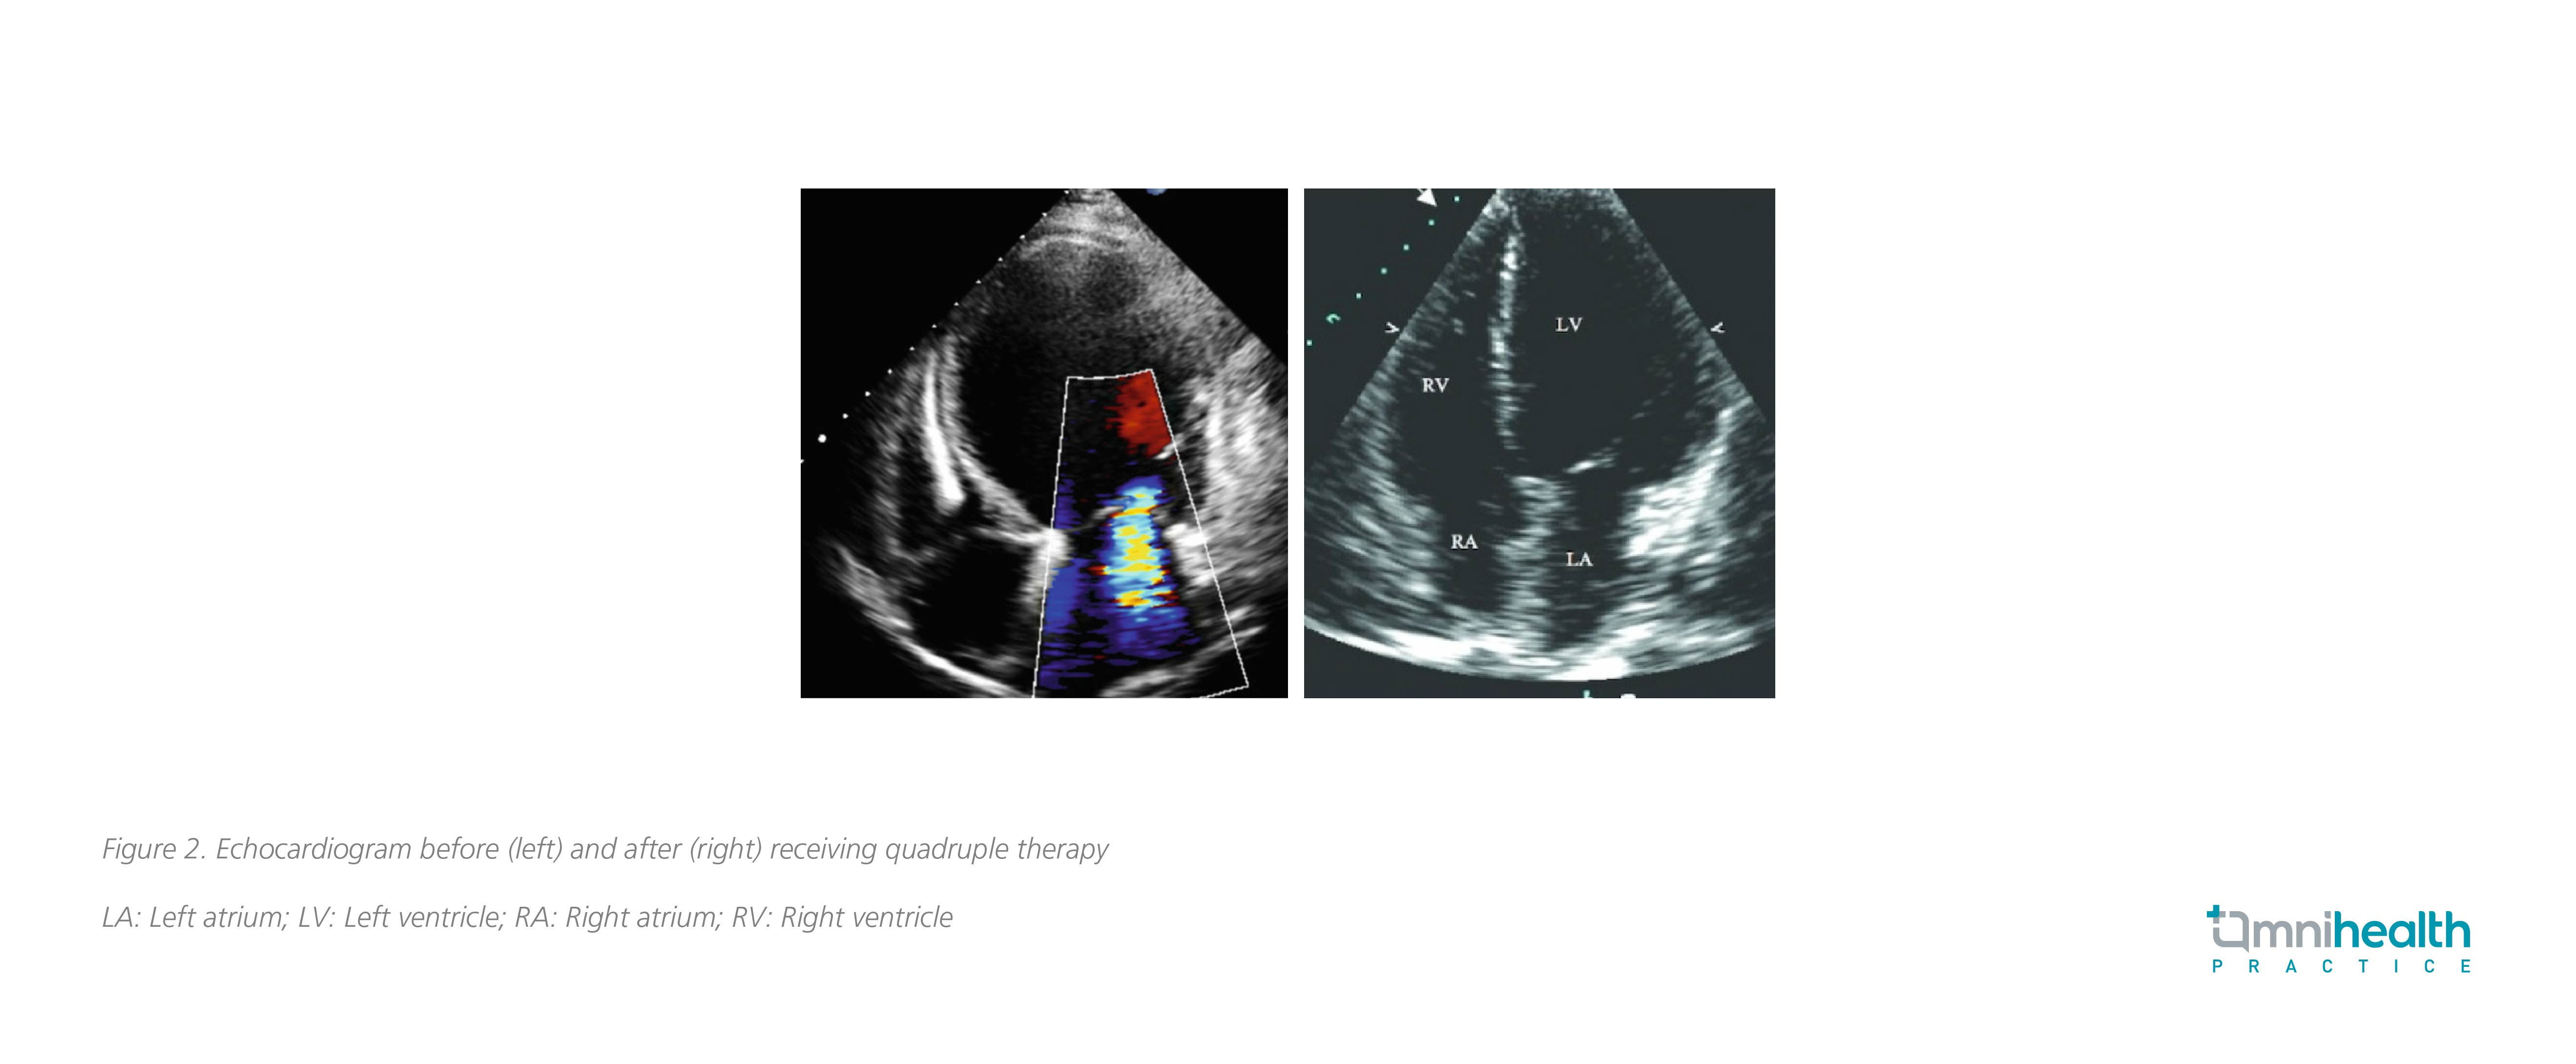

Echocardiogram showed a reduced ejection fraction of 25-30% with a significantly dilated left ventricle (LV). Moderate functional mitral regurgitation was observed, and computed tomography (CT) coronary angiogram showed normal coronary arteries. Initially, he was given intravenous furosemide and his HF symptoms were partially improved. With reference to the results of DAPA-HF which dapagliflozin showed a significant reduction of cardiovascular death or HF-related hospitalization among HFrEF patients, she was given a combination of low-dose ARNI, β-blocker, MRA and 10mg dapagliflozin daily during his hospital stay. The quadruple treatment was well-tolerated with no significant decrease in blood pressure.

With symptoms under control and NYHA status improved to class I/II, he was discharged after 1 week of hospitalization. ARNI and β-blockers were then titrated to the maximum target dose during follow-up. Then 4 months later, echocardiogram showed a decreased LV size with ejection fraction improved to 45%, suggesting that quadruple treatment including dapagliflozin may improve LV remodeling (Figure 2).